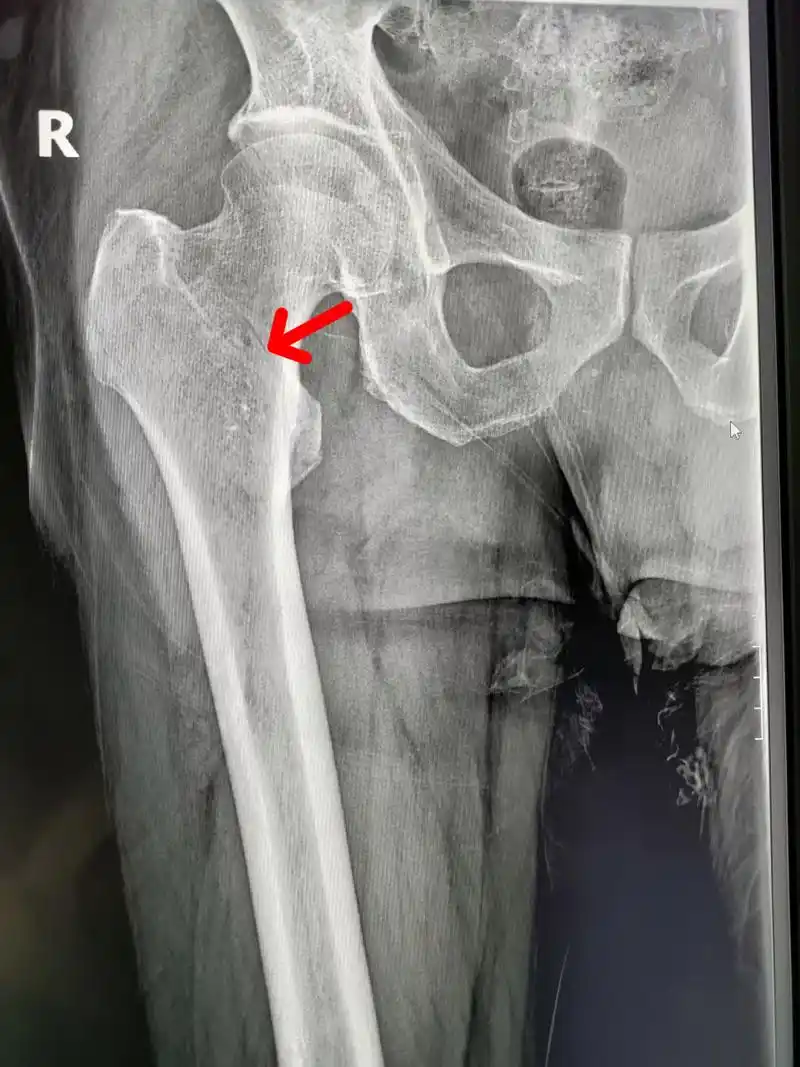

男,67岁,因滑倒就诊,右股骨粗隆间骨折,就是我们老百姓说的大腿根的